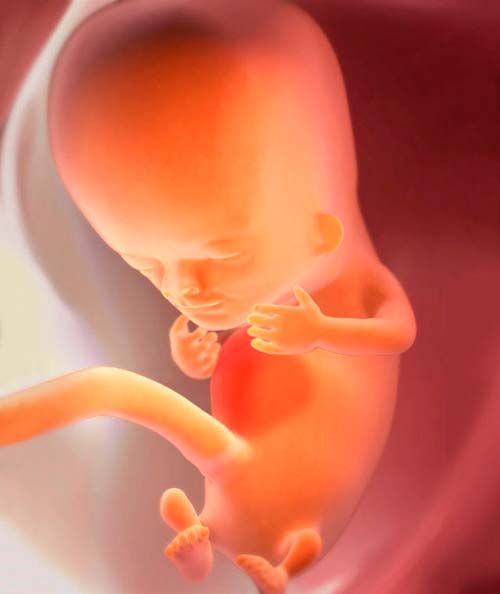

Désormais, l'enfant à naître n'est plus considéré comme un embryon. Médicalement, c'est un fœtus. Et en apparence - un petit homme à grosse tête de la taille d'une grosse fraise. La longueur du petit corps est d'environ 31 à 42 mm et le poids est d'environ 5 g.

- Le fœtus n'a pas encore d'os pleins, seulement du cartilage. Sa densité commence à augmenter.

- Le visage est déjà formé, mais les muscles du visage, du pharynx et du cou commencent tout juste à se développer.

- Les rudiments des futurs poils apparaissent dans tout le corps.

- Dans le cervelet, des connexions neuronales se développent qui «commanderont» plus tard les réflexes.

- Le cœur fonctionne dans un mode amélioré et fait 150-170 battements par minute.

- L'enfant bouge activement: se penche, étend les membres, peut même commencer à sucer un doigt. Si les jambes touchent les parois de la vessie fœtale, le bébé est tout à fait capable de repousser. Mais cela ne se ressent pas - l'enfant est trop petit.

- Les petites oreilles sont presque complètes.

- Le système nerveux commence à se diviser en central et périphérique.

- Un diaphragme est formé - un muscle spécial qui sépare la poitrine et la cavité abdominale.

- Les rudiments des dents primaires se développent progressivement.

- Habituellement, la queue disparaît.